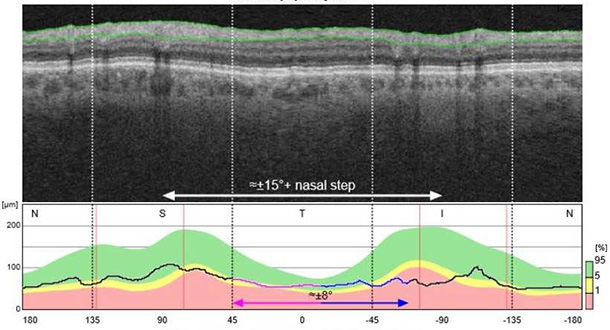

La tomografía de coherencia óptica (OCT) es una tecnología no invasiva que, en pocos segundos y sin radiación, nos permite obtener imágenes de alta resolución de distintas estructuras del globo ocular sin siquiera tocar el ojo.

Las imágenes que produce la OCT nos aportan mucha información sobre la estructura interna del ojo pero, básicamente, lo que nos permiten es medir los grosores de la capa de células ganglionares y la capa de fibras nerviosas retinianas, de donde se origina el nervio óptico.

Para comparar los resultados con una base de datos de población de referencia, y al repetirla periódicamente, comparar al paciente consigo mismo. Esta observación de la evolución de los resultados permite valorar si empeora o no, y ayuda a tomar decisiones con respecto al tratamiento.

La posibilidad de hacer estas mediciones de forma reproducible ha hecho de la OCT una herramienta muy poderosa para el diagnóstico y seguimiento del glaucoma, probablemente la más utilizada en este momento.